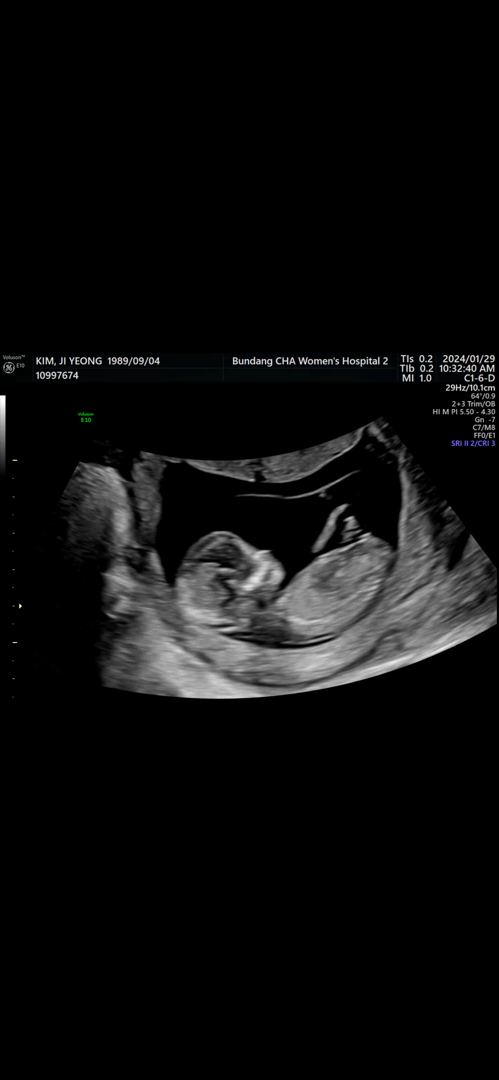

12주 울 햇살이 각도법으로 성별?!

12주때 초음파구용 아직까지 16주되려면 2주 더 기다려야하내요ㅜㅡㅜ 넘 궁금한 성별! 각도법으로 한번 봐주세여 ㅎ